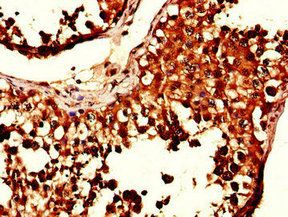

Immunohistochemistry of paraffin-embedded human testis tissue slide using orb631187 (SIK1 Antibody) at dilution of 1:50.